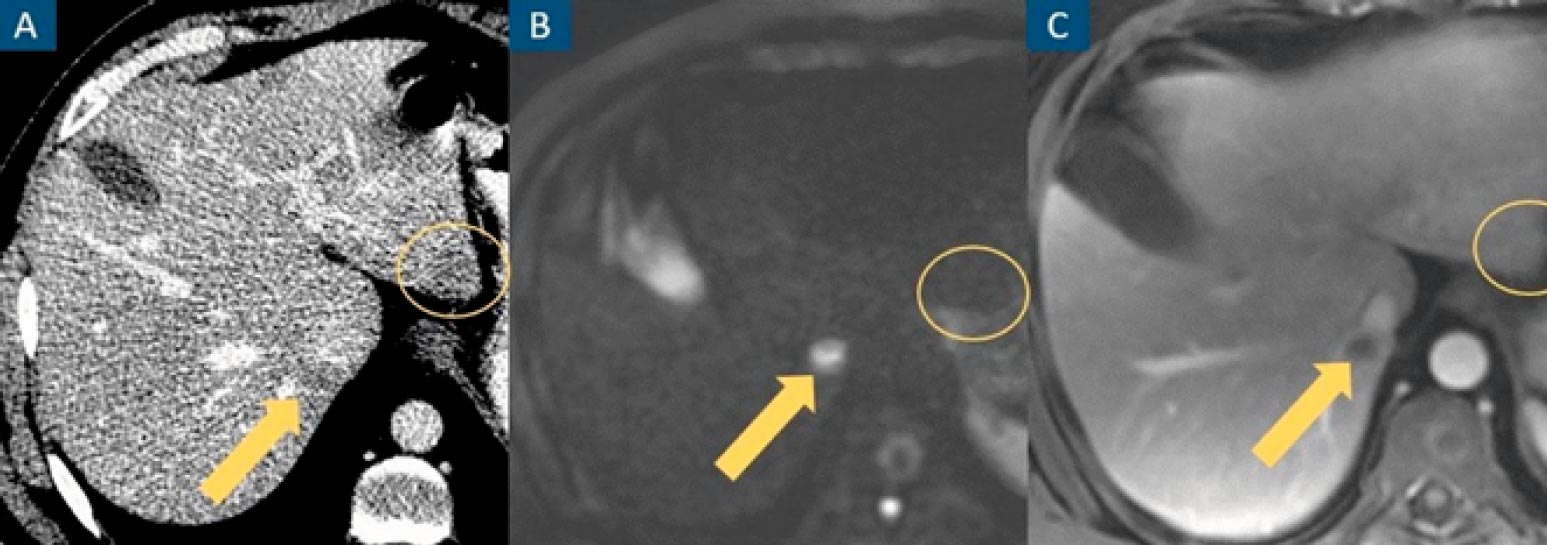

Figure 1: CT misses a true hepatic lesion and detects a pseudolesion. Axial contrast-enhanced venous phase CT image (A), axial diffusion-weighted image at b=1000 (B) and axial contrast-enhanced portal venous phase fat-suppressed T1-weighted image (C). A hepatic nodule (arrow) is inconspicuous on CT and evident on MRI. An apparent hepatic nodule on CT (circle) has no expression on MRI.